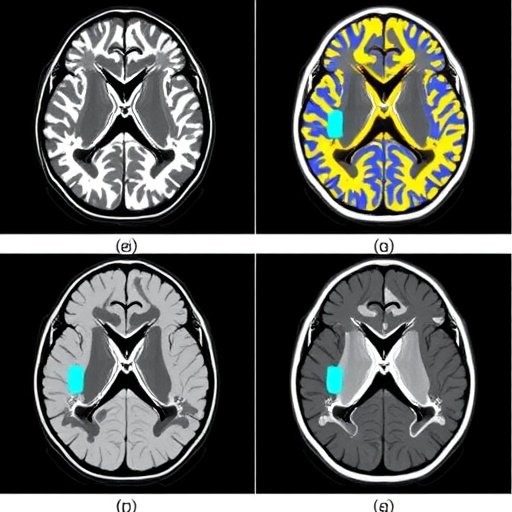

In their study, Peng and colleagues conducted a series of comparisons between the traditional MRI reconstruction methods and their newly developed deep learning-based approaches. The aim was to objectively assess the differences in image quality and the subsequent impact on diagnostic efficacy. By utilizing pediatric participants diagnosed with hippocampal sclerosis, the study provided a solid clinical backdrop to examine these technological advancements.

One key aspect of this research was the rigorous methodology employed to rank and evaluate the quality of the MRI images produced by both methodologies. The study not only involved subjective assessments from radiologists but also quantitative metrics, including signal-to-noise ratios and other imaging parameters that can indicate the clarity and resolution of the captured images.

Results from this comprehensive analysis indicated a clear trend: deep learning-based reconstruction techniques yielded images of superior quality when compared to those generated through conventional methods. The enhanced quality of deep learning images allowed for more accurate and detailed visualizations of hippocampal structures, aiding clinicians in making more informed diagnostic decisions.

Moreover, the researchers explored how these technological advancements could influence clinical practice in pediatric neurology. They posited that the enhanced imaging capabilities would allow for improved differentiation of various pathologies, which is essential for tailoring treatment strategies in children suffering from diverse neurological conditions. For instance, the ability to accurately visualize subtle anatomical changes in the hippocampus could significantly alter treatment plans for patients with epilepsy stemming from hippocampal sclerosis.